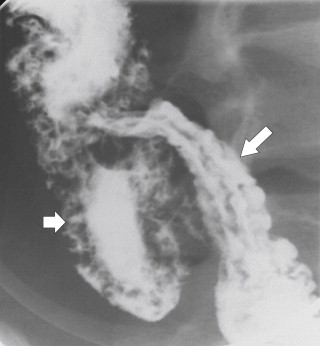

The imaging features depend on the stage of the disease ( Table 5-2 ), and many of these features are shared by Crohn disease ( Table 5-3 ). They can sometimes be identified by plain abdominal radiography as thickened haustra, particularly when caused by a pancolitis ( Fig. 5-5 ). Severe disease can almost certainly be recognized on plain radiography as can toxic megacolon, with marked colonic distention resulting from ileus ( Fig. 5-6 ) and wall and mucosal thickening ( Fig. 5-7 ). The wall thickening is sometimes referred to as “thumb-printing” because of the polypoid soft tissue nature of the mucosal edema and thickening. BE demonstrates typical features but has largely been replaced by optical colonoscopy for diagnosis. When BE is performed, the features depend on the severity and acuity of disease. In acute disease a variable length of colon (starting in the rectum) shows a granular mucosal pattern representing edema and ulcer formation, sometimes of the whole colon ( Fig. 5-8 ), which may also affect the last few centimeters of the terminal ileum (“backwash ileitis”) ( Fig. 5-9 ). “Collar-button ulcer” formation has been described, which represents acute ulceration of the colon with submucosal extension ( Fig. 5-10 ), with further ulceration prevented by the relatively impermeable bowel wall. This sign is three times as common in UC as in Crohn disease. Pseudopolyp formation, which can also be recognized in Crohn disease, can occur with more chronic disease and represents areas of reparative mucosa between areas of ulceration ( Fig. 5-11 ). As the disease progresses, the affected length of colon becomes featureless and shortened, termed “lead piping” ( Fig. 5-12 ).

Figure 5-21, A, BE in a 36-year-old woman with numerous apthous ulcers ( arrows ) in the left colon from Crohn disease. B, Magnified view of apthous ulcers ( arrow ) in the distal transverse colon.